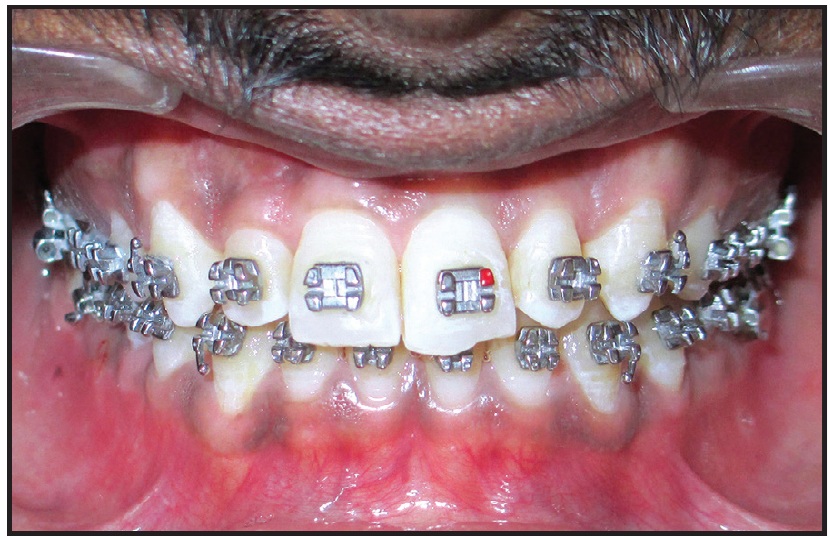

The lower arch was bonded with an .022" × .028" MBT* appliance, and an .012" round nickel titanium archwire was placed. Three months later, the wire size was increased to .014" for two more months of leveling. Since growth appeared to be complete, a 2 × 4 appliance was then bonded in the upper arch for correction of the upper incisor inclination (Fig. 2). The patient was asked to wear a removable posterior bite plate (7mm thick in the premolar region) for one month while sleeping, followed by an additional six hours of wear every day for four months.

Fig. 2 After five months of leveling with lower .022" × .028" MBT* appliance and nickel titanium archwires, 2 × 4 appliance placed in upper arch.